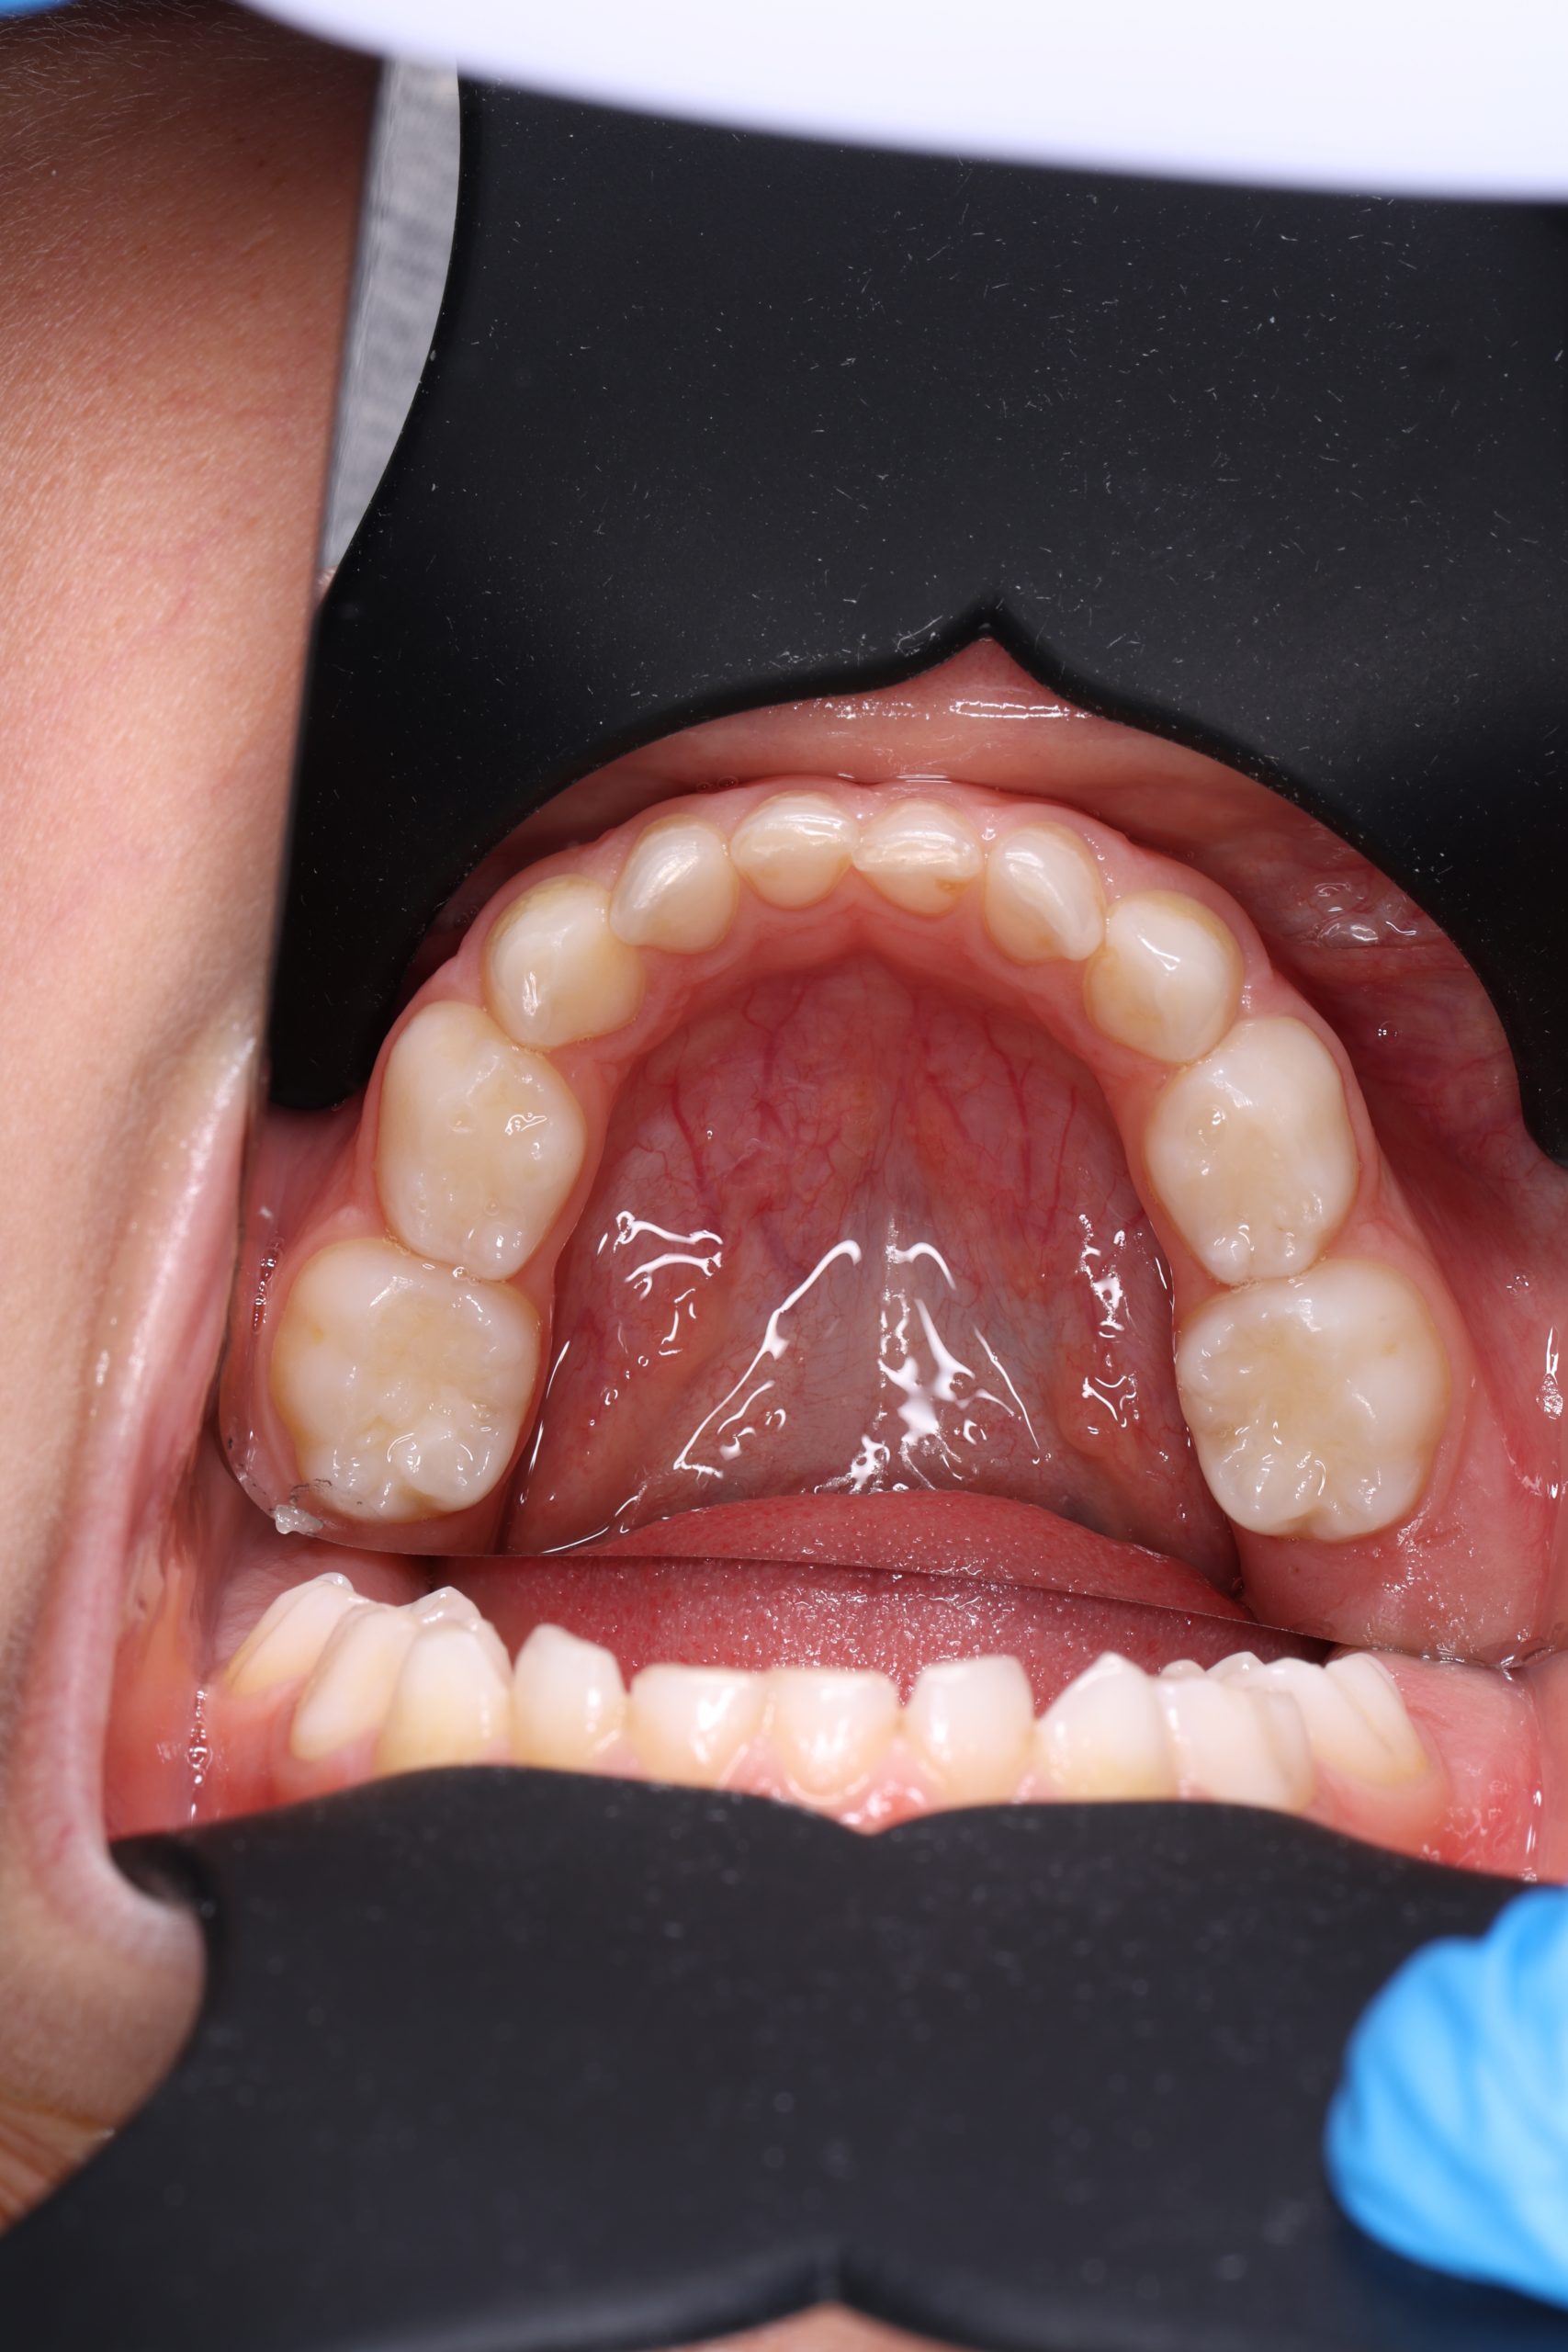

Our dentists perform root canal therapy every day. Complex anatomy and retreatments are routine. Each difficult case is planned by our senior clinician to ensure the right strategy from the start. - Microscope precision and isolation

Under bright magnified light, a tiny opening is created and every canal located — even the hidden ones that often cause failures elsewhere. - Cleaning and shaping